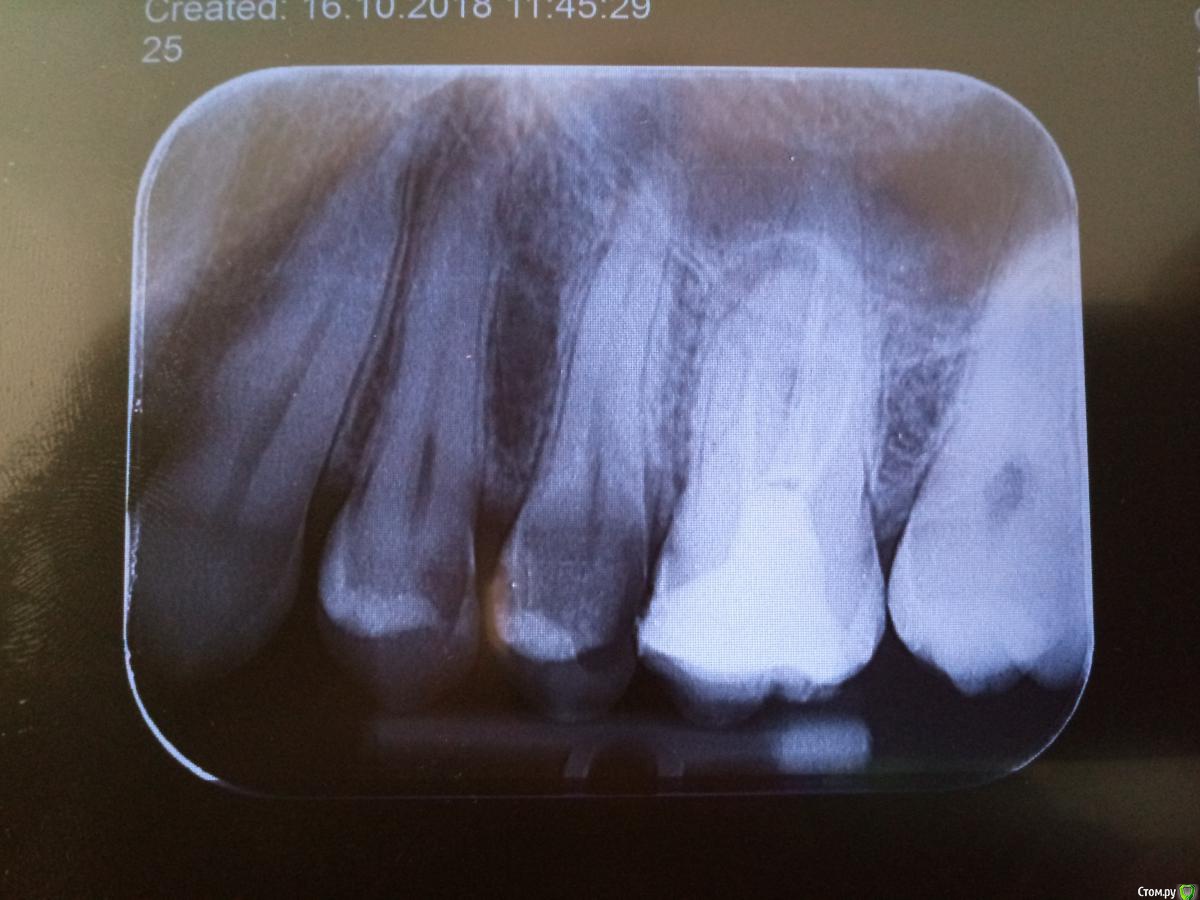

Studentic Опубликовано 18 октября, 2018 Поделиться Опубликовано 18 октября, 2018 (изменено) Сдравствуйте, доктора! На днях имел следующий случай: хронический пульпит на 25 зубе. Ввиду близкого расположения к синусу, боялся полностью пройти каналы, чтоб не разбить верхушку, поэтому, по показателям апекслокатора, прошел канал на глубину где-то между 0.5 и 00. Использовал NiTi к-файлы 15, 20, 25. 25 файлом не смог пройти на ту глубину куда свободно проходил белый и желтый файлы, почему-то клинило на пару мм выше. Промыв хорошо 5% гипохлоритом, по отсутствию альтернативы, пломбировал канал резорцин-формалиновой смесью, пропустив этап импрегнации. Пройденная длина 15 и 20 файлом - 22 мм, по тношению к длине корня на снимке получается короче на 1 - 1.5 мм чем было необходимо чтобы быть на уровне радиологической верхушки. Скажите пожалуйста, какие могут быть прогнозы? Снимка после лечения пока нету, но в скором времени получу его и добавлю.На второй день после лечения пациент сказал что есть очень слабая чувствительность при накусывании. Изменено 18 октября, 2018 пользователем Studentic Ссылка на комментарий

Kolchanov Опубликовано 18 октября, 2018 Поделиться Опубликовано 18 октября, 2018 Ну какие там прогнозы. Судя по rg там и до лечения уже пи...ц зубу. Потом удалите, распилите, посмотрите. Хорошая тренировка будет. 1 Ссылка на комментарий

Studentic Опубликовано 18 октября, 2018 Автор Поделиться Опубликовано 18 октября, 2018 (изменено) Ну какие там прогнозы. Судя по rg там и до лечения уже пи...ц зубу. Потом удалите, распилите, посмотрите. Хорошая тренировка будет.Да, зуб и до моего "лечения" был в очень плохом состоянии, но я переживаю, чтоб из-за меня больной не получил проблемы с пазухой, да и в принципе, это мой первый зуб с столь близким отношением к пазухе, и опыта в таких ситуациях у меня нету. Как вы думаете, мне следовало действовать как-нибудь иначе, не обладая ничем другим кроме выше перечисленных материалов? Изменено 18 октября, 2018 пользователем Studentic Ссылка на комментарий